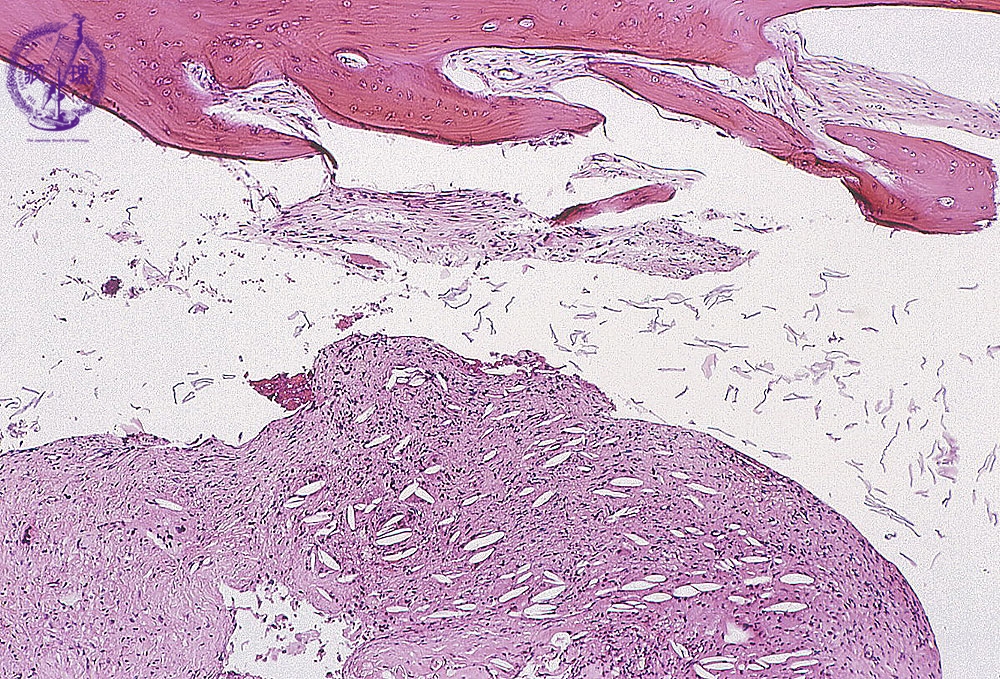

- (1)cholesteatoma, otitis media

Bone fragments and fibrous granulation tissues are seen. Cholesterol clefts are also seen in the granulation tissue (arrow).